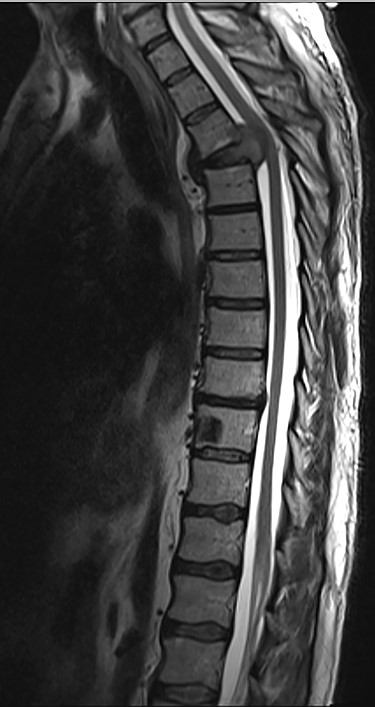

Sagottal T2W MRI showing synchronous lytic lesions in T10 & L3 vertebral bodies.